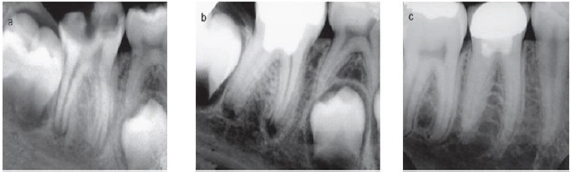

Figure 8: Apeification with MTA as apical plug.

A) The canal is disinfected with copious irrigation.

B) Calcium phosphate is placed through the apex as a barrier.

C) 4mm of MTA is places at the apex.

D) The canal is filled with thermoplastized gutta-percha.

E) Bonded resin resorted is placed at level below CEJ.

Figure 9: Calcium hydroxide and periapical changes.

a) Infected pulp and inflammation.

b) The high PH generates a zone liquefaction necrosis and a zone of coagulation necrosis.

c) New hard tissue forming cells from periapical tissue and formation of cementoid and osetoid tissue.

d) Root filling with gutta-percha, notice vascular inclusion within hard apical barrier.

Figure 10: Mineral trioxide aggregate and pulpal responses.

a) MTA induce release of wound healing signals.

b) High PH generates a very narrow zone of coagulation necrosis.

c) Next to that zone reparative dentinogenesis zone is formed.

Figure 11: Revitalization procedure.

a) Preoperative radiograph with periapical lesion and open apex.

b) After 3 months elongation with periapical lesion and open apex.

c) After 8 months shows narrowing if apex and thickening of dentine walls.

d) After 18 months shows healing of lesion and apical closure.